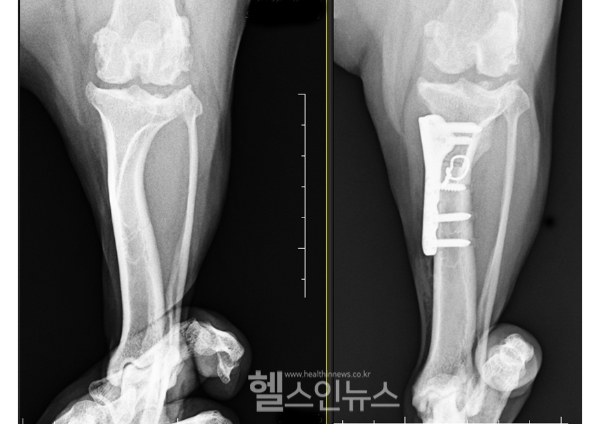

십자인대 파열 수술 방법은 다양하다. 가장 일반적으로 하는 수술방법은 인공인대재건술이다. 손상된 십자인대를 제거하고 십자인대의 역할을 대신 해 줄 인공 인대를 삽입하는 방법으로 진행된다. 하지만 체중이 많이 나가거나 활동성이 큰 아이들은 인공 인대가 안정적이지 않을 수 있기 때문에 경골 고위의 각도를 조정시켜 체중 부하 시 슬관절의 안정성을 확보하는 해 주는 절골 수술을 권한다. 경골을 절골하는 방식에 따라 TPLO, CTWO, CBLO 등으로 나뉘지만 목표하는 바는 동일하기 때문에 수술 결과도 대동소이하다. 수술 방법 선택은 반려동물의 나이, 파열 정도, 건강 상태 등에 따라 달라질 수 있다. 따라서 수의사와의 상담을 통해 최적의 치료 방법을 결정해야 한다.